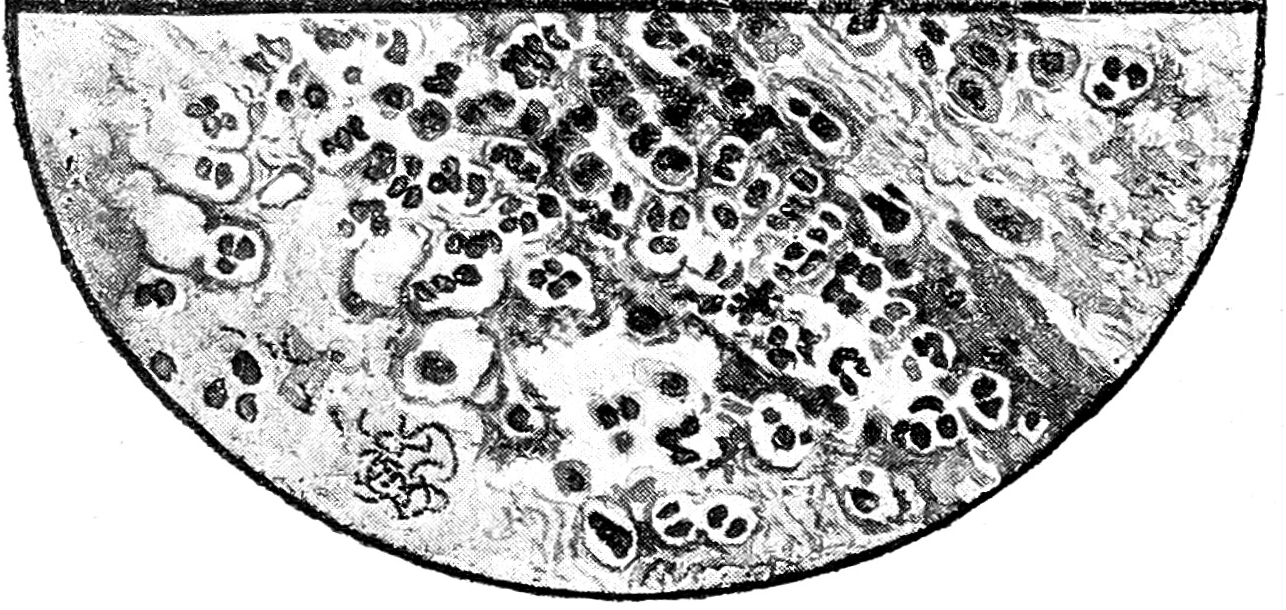

Рис. 4. Катарральный бронхит. Фон слизистый, много N, хорошо сохранившиеся 2 клетки плоского эпителия.

Рис. 5. Хронический бронхит. Фибриллярный фон, большое количество N.

Бронхит. Почти всякое легочное заболевание сопровождается катарром бронхов в той или иной степени, что отражается и на цитологической картине мокроты. Острый катарральный бронхит, макроскопически давая слизистую, слизисто-гнойную или гнойную мокроту, микроскопически дает однообразную картину: все поле зрения представляет фиолетово-розовый фон с сеткой из параллельно расположенных фибрилл, в которой, как и на основном фоне, выступает большое количество сравнительно хорошо сохранившихся нейтрофилов и бактерий. Фибриллярная сетка одинакового с фоном цвета, является результатом дегенерации нейтрофилов и эпителия бронхов. Клетки последнего в легких случаях бронхита встречаются в мокроте довольно редки, так как они вообще появляются здесь только при резких кашлевых толчках или при деструктивных процессах. Моноцитоподобных клеток в острых и легких случаях бронхита обыкновенно в мокроте не бывает, или, если они встречаются, то в единичных экземплярах.

Затянувшиеся бронхиты и бронхиты при эмфиземе легких с обильным количеством мокроты дают цитологическую картину подобную той, которая наблюдается в острых случаях, только фибриллярная сетка здесь бывает более резко выражена.